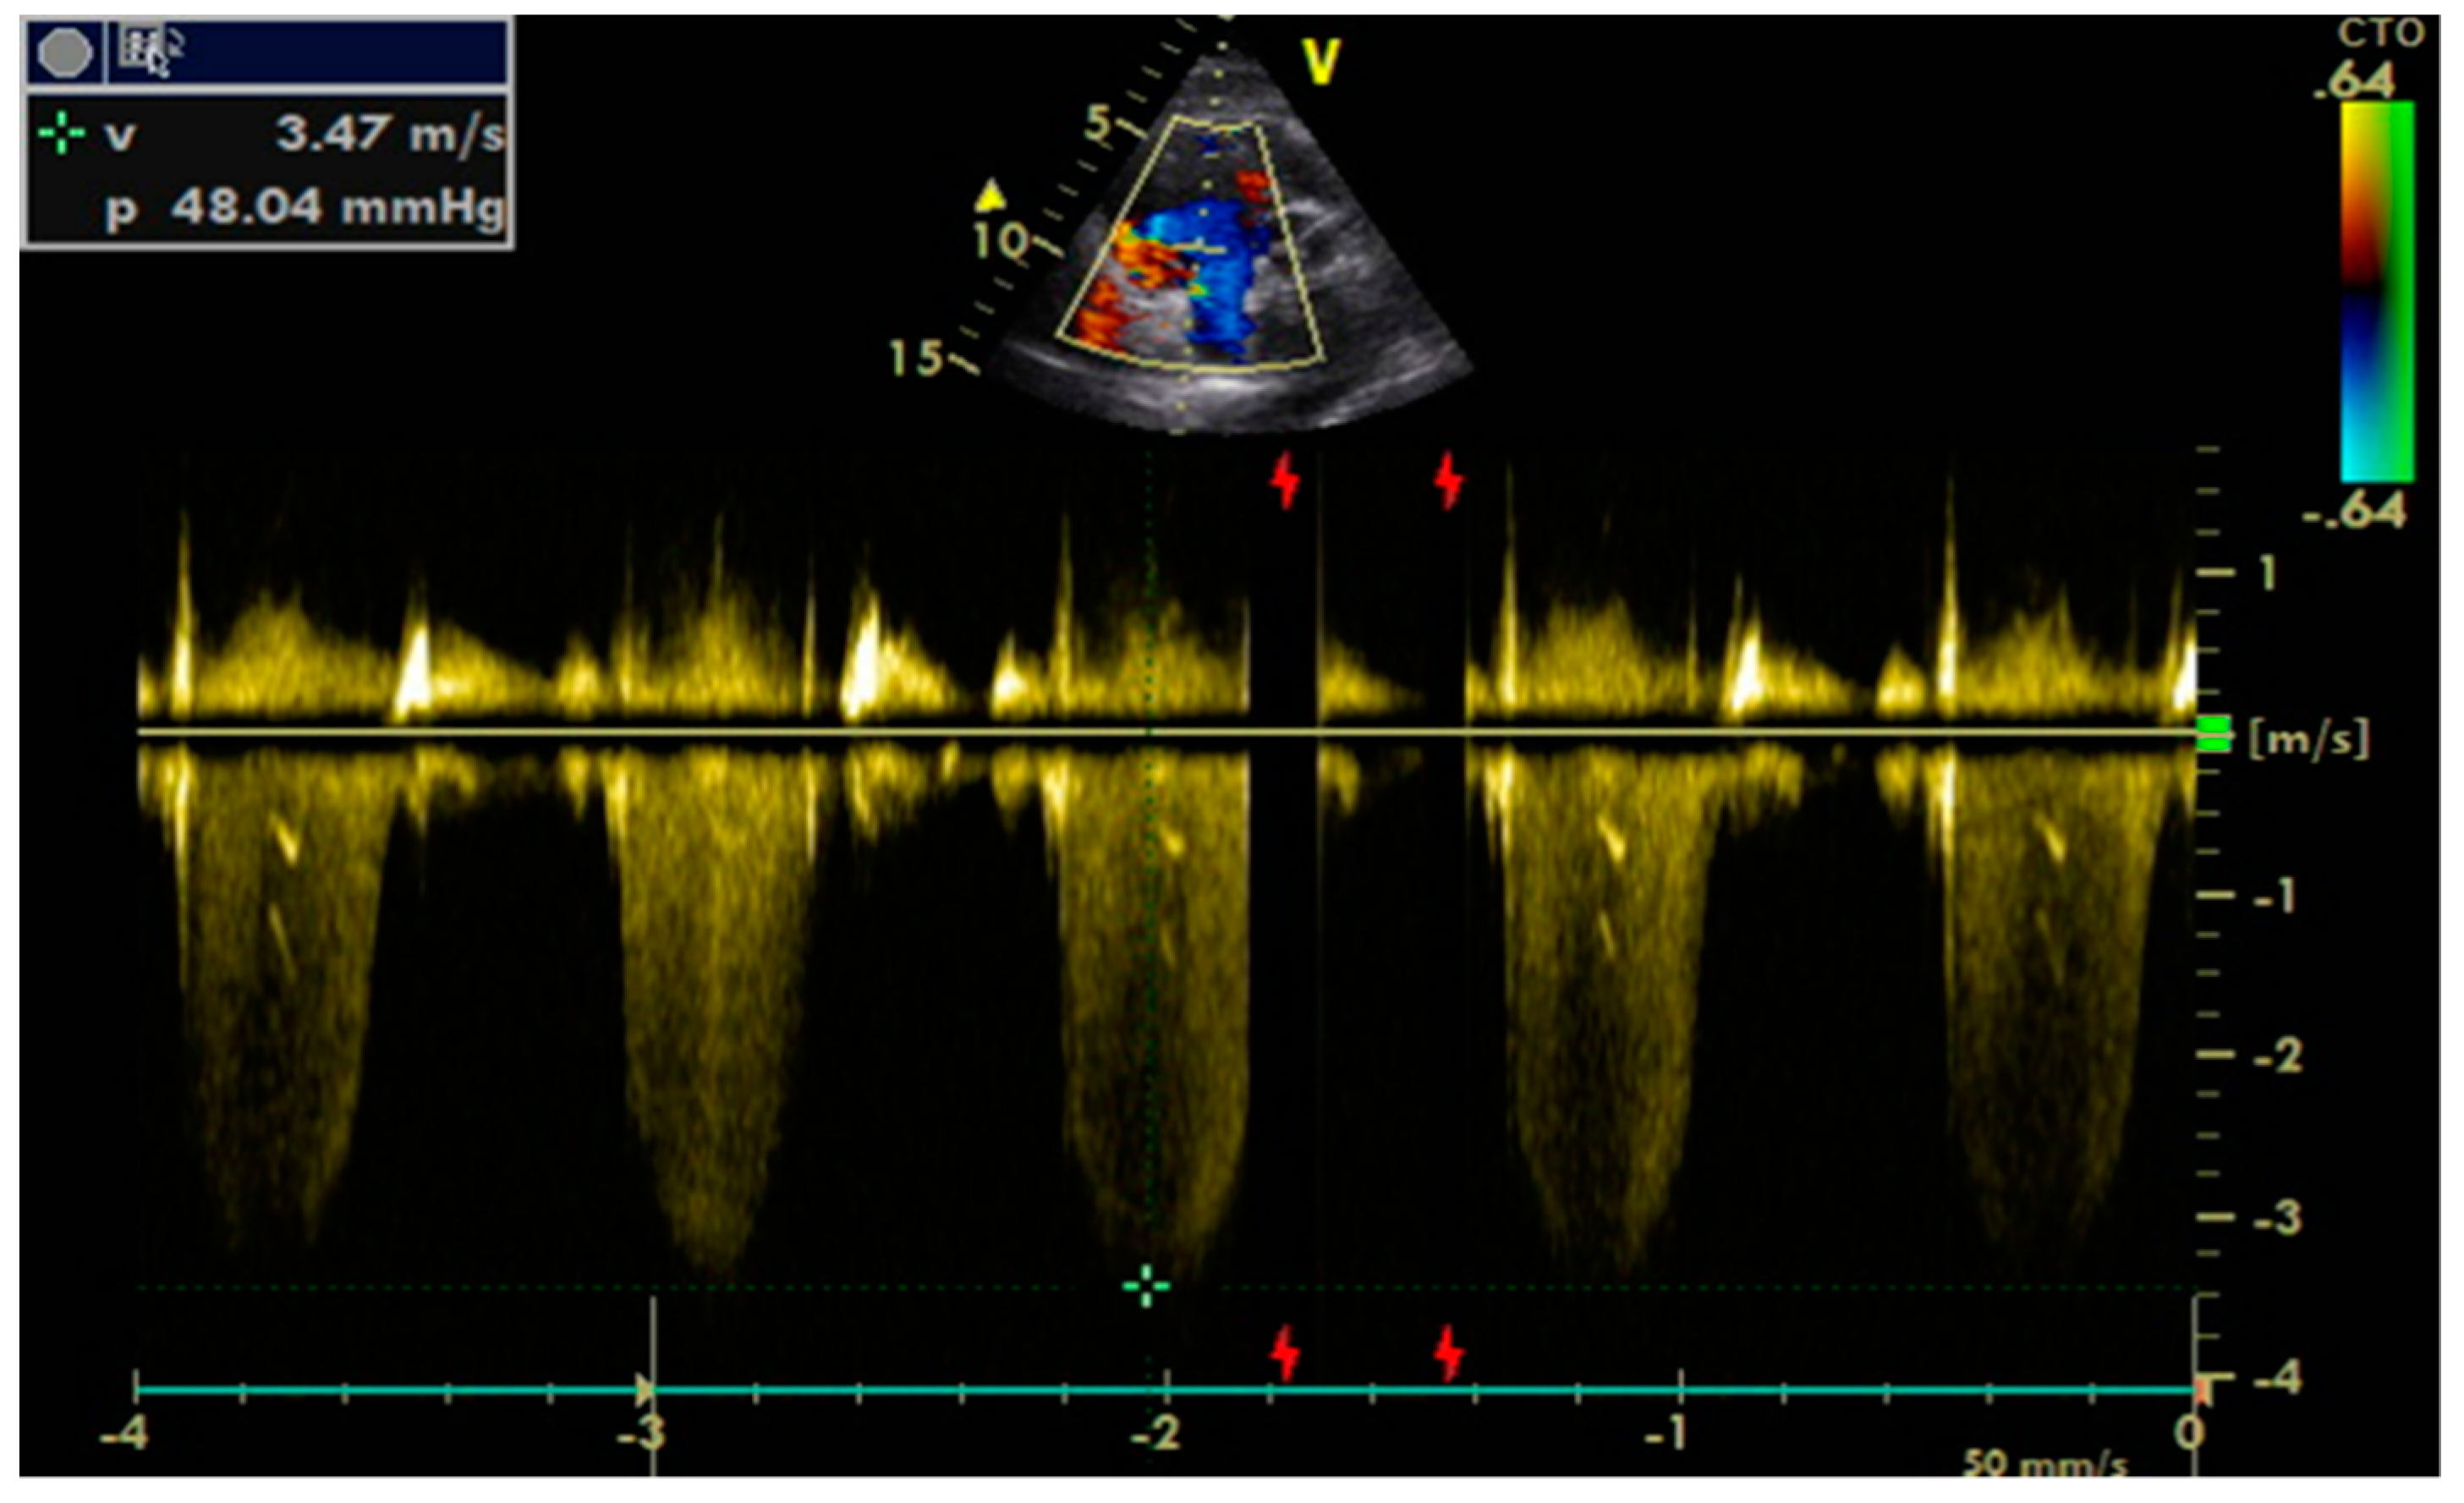

- Tricuspid regurgitation peak velocity (TRpV; Figure 5) with CW (continuous Doppler) on tricuspid regurgitation jet;